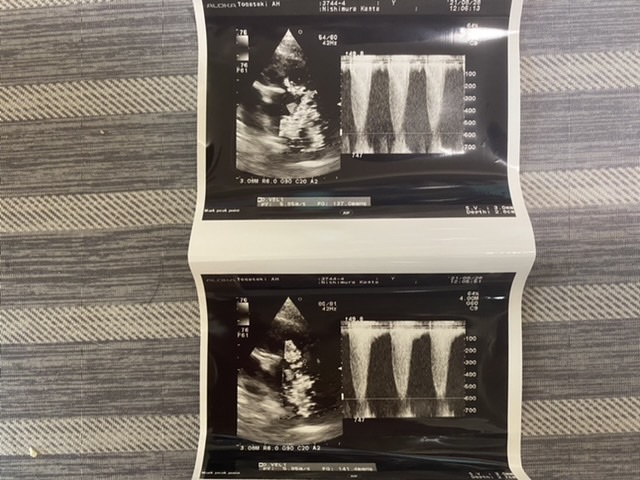

こちらエコーになります。

普通穏やかなカーブの波なのが鋭く

尖っているのが血液が上手く流れていない

状態になります。